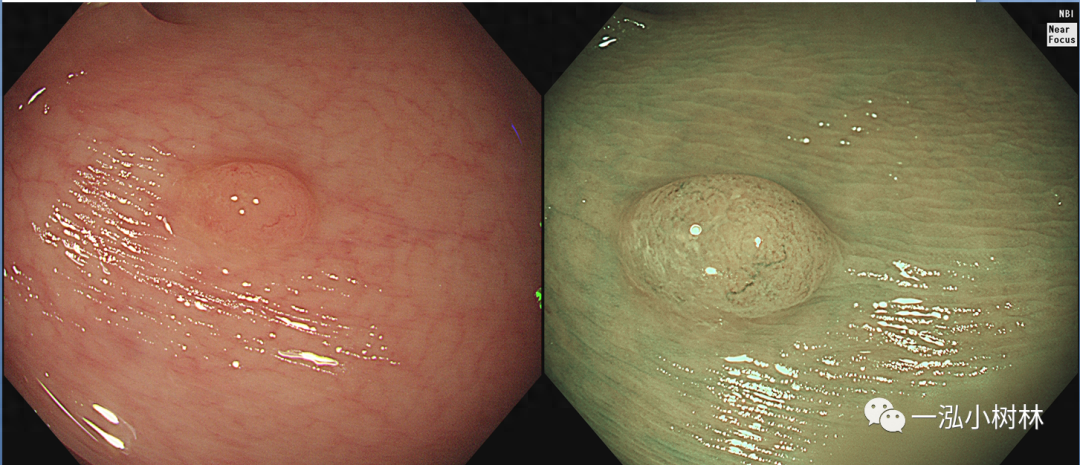

图1 结肠管状腺瘤(JNET2A型)